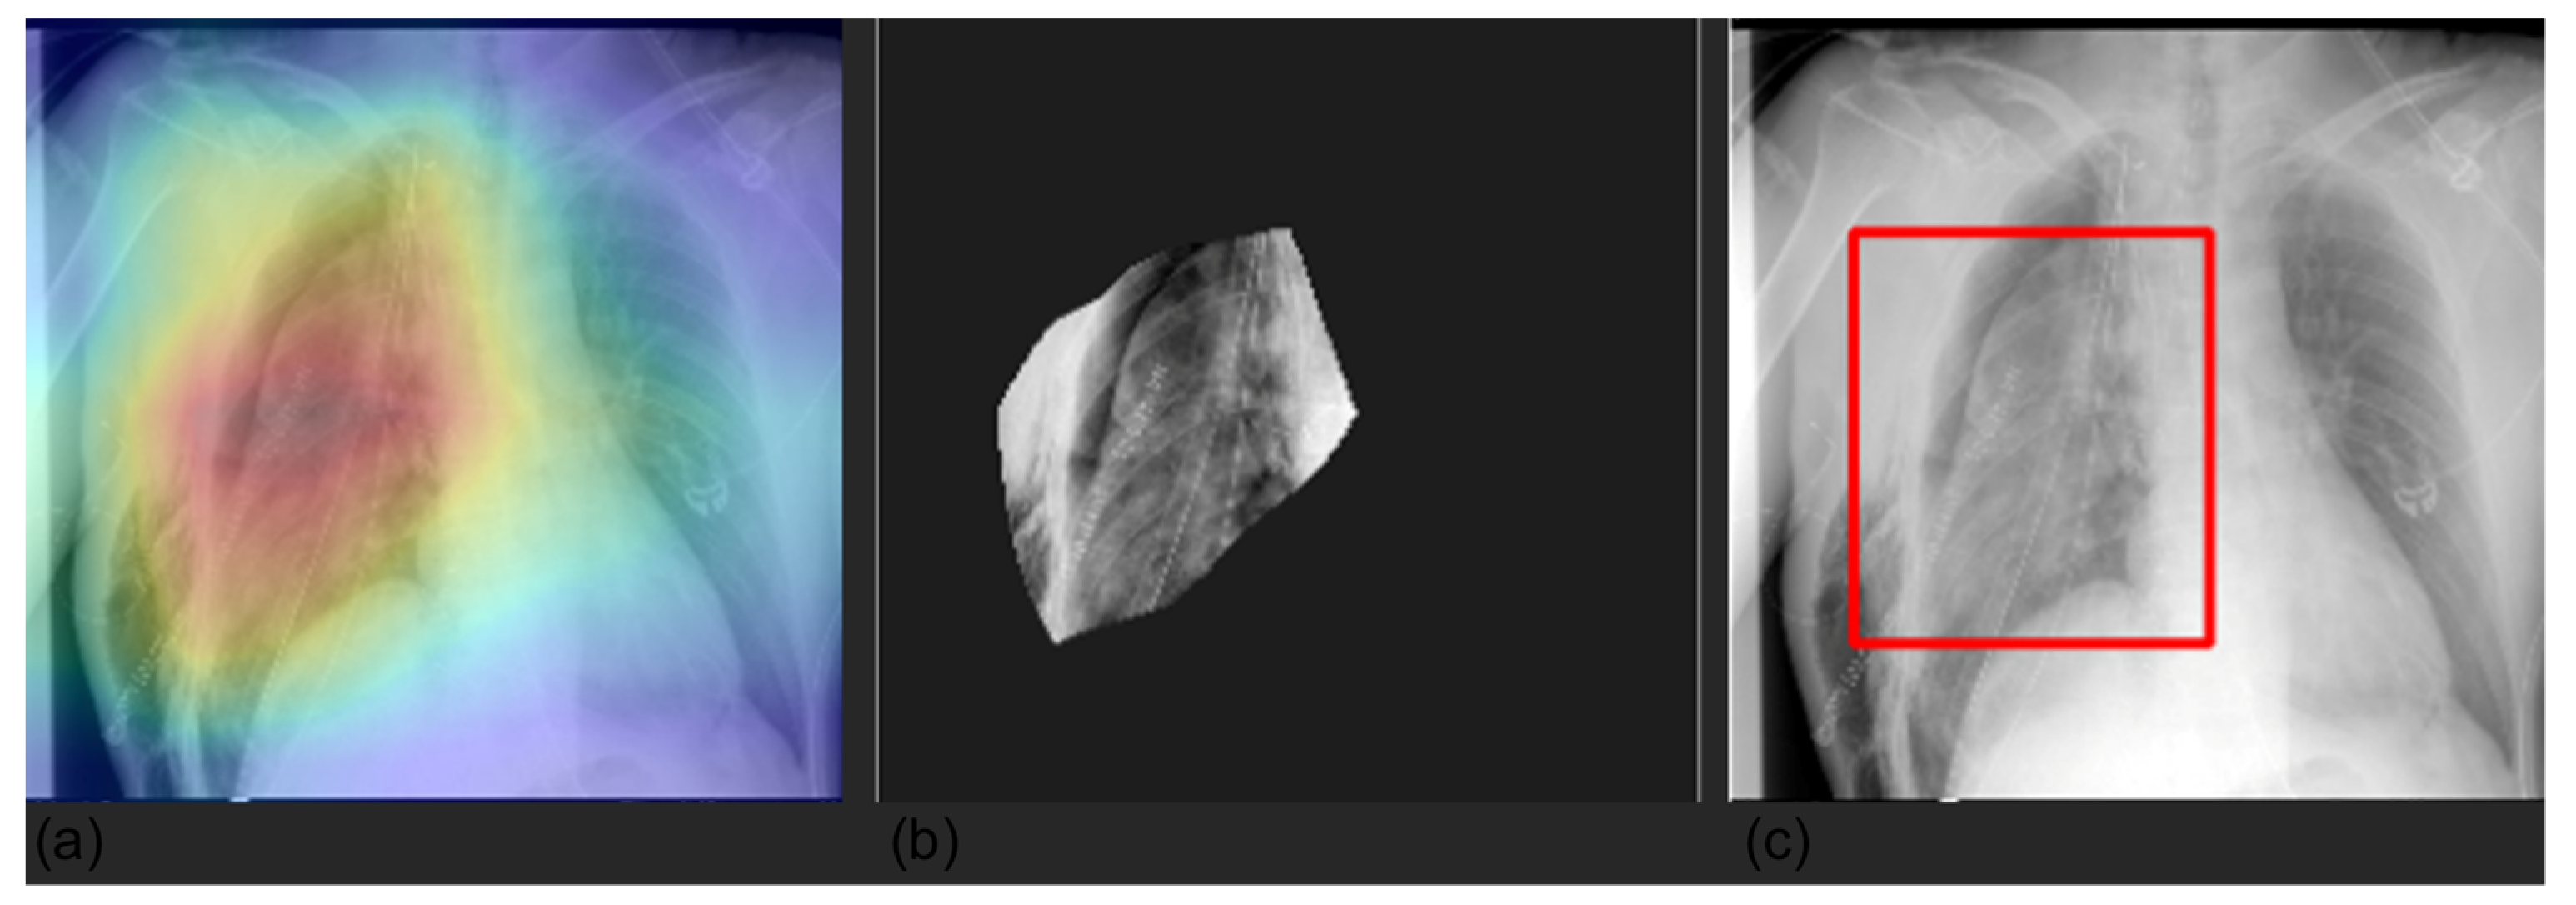

2.5. Explainability

3.4. Grad-CAM